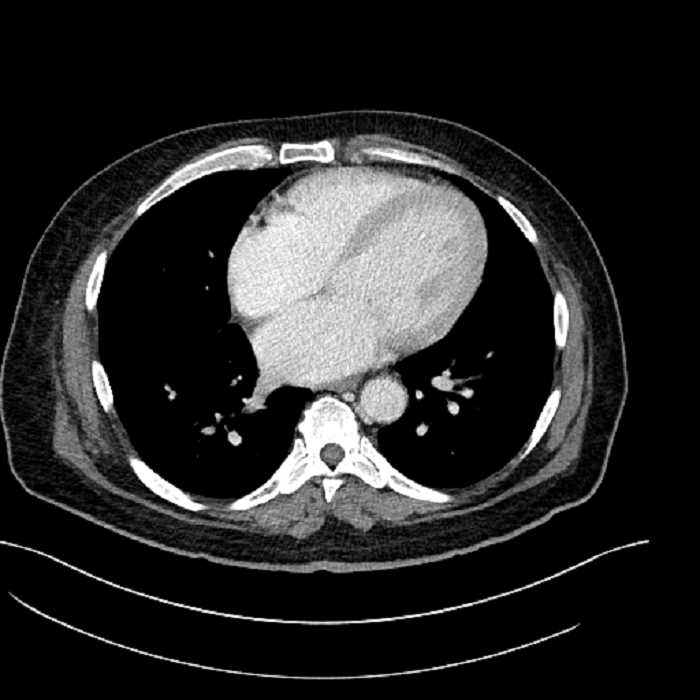

• Lower chest

• Mild cardiomegaly

• Mild dependent atelectasis